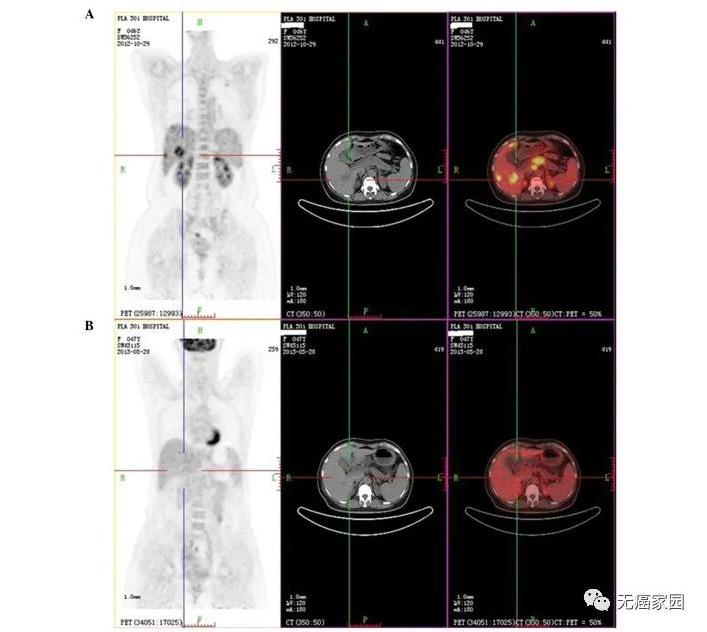

晚期胰腺癌肝转移病灶消失,胰头肿瘤减少50%,基因检测功不可没 胰腺癌

胰腺癌晚期胰腺癌肝转移病灶消失,胰头肿瘤减少50%,基因检测功不可没

2013年11月,一位62岁的美国男性因体重减轻与无痛性黄疸诊治,无用药史。胸部的CT扫描,腹部和骨盆检查发现肝脏肿块和假定胰腺肿块。他接受了内镜逆行胰胆管造影(ERCP)和置入金属支架,症状明显改善。之后,CT引导下肝肿块穿刺活检。病理学检查中度分化腺癌,源于原发性胰腺。患者接受吉西他滨和厄洛替尼,病情稳定两个月,因副作用而停药。病人持续性疲乏、体重减轻

在2015年秋天,44岁的年轻人Doron Broman被诊断患有胰腺癌 - 并且惊讶地发现他的胰腺癌已经转移到肝脏上一个大肿瘤。 医生曾断言,他只有几个月的生存期,而两年后,Doron Broman的影像学检查显示,肿瘤已经奇迹般全部消失了!也许这在过去纯属天方夜谭,而在精准医疗迅速发展的今天,一切皆有可能。  胰腺癌一直被公认为“癌症之王”,对于这种预